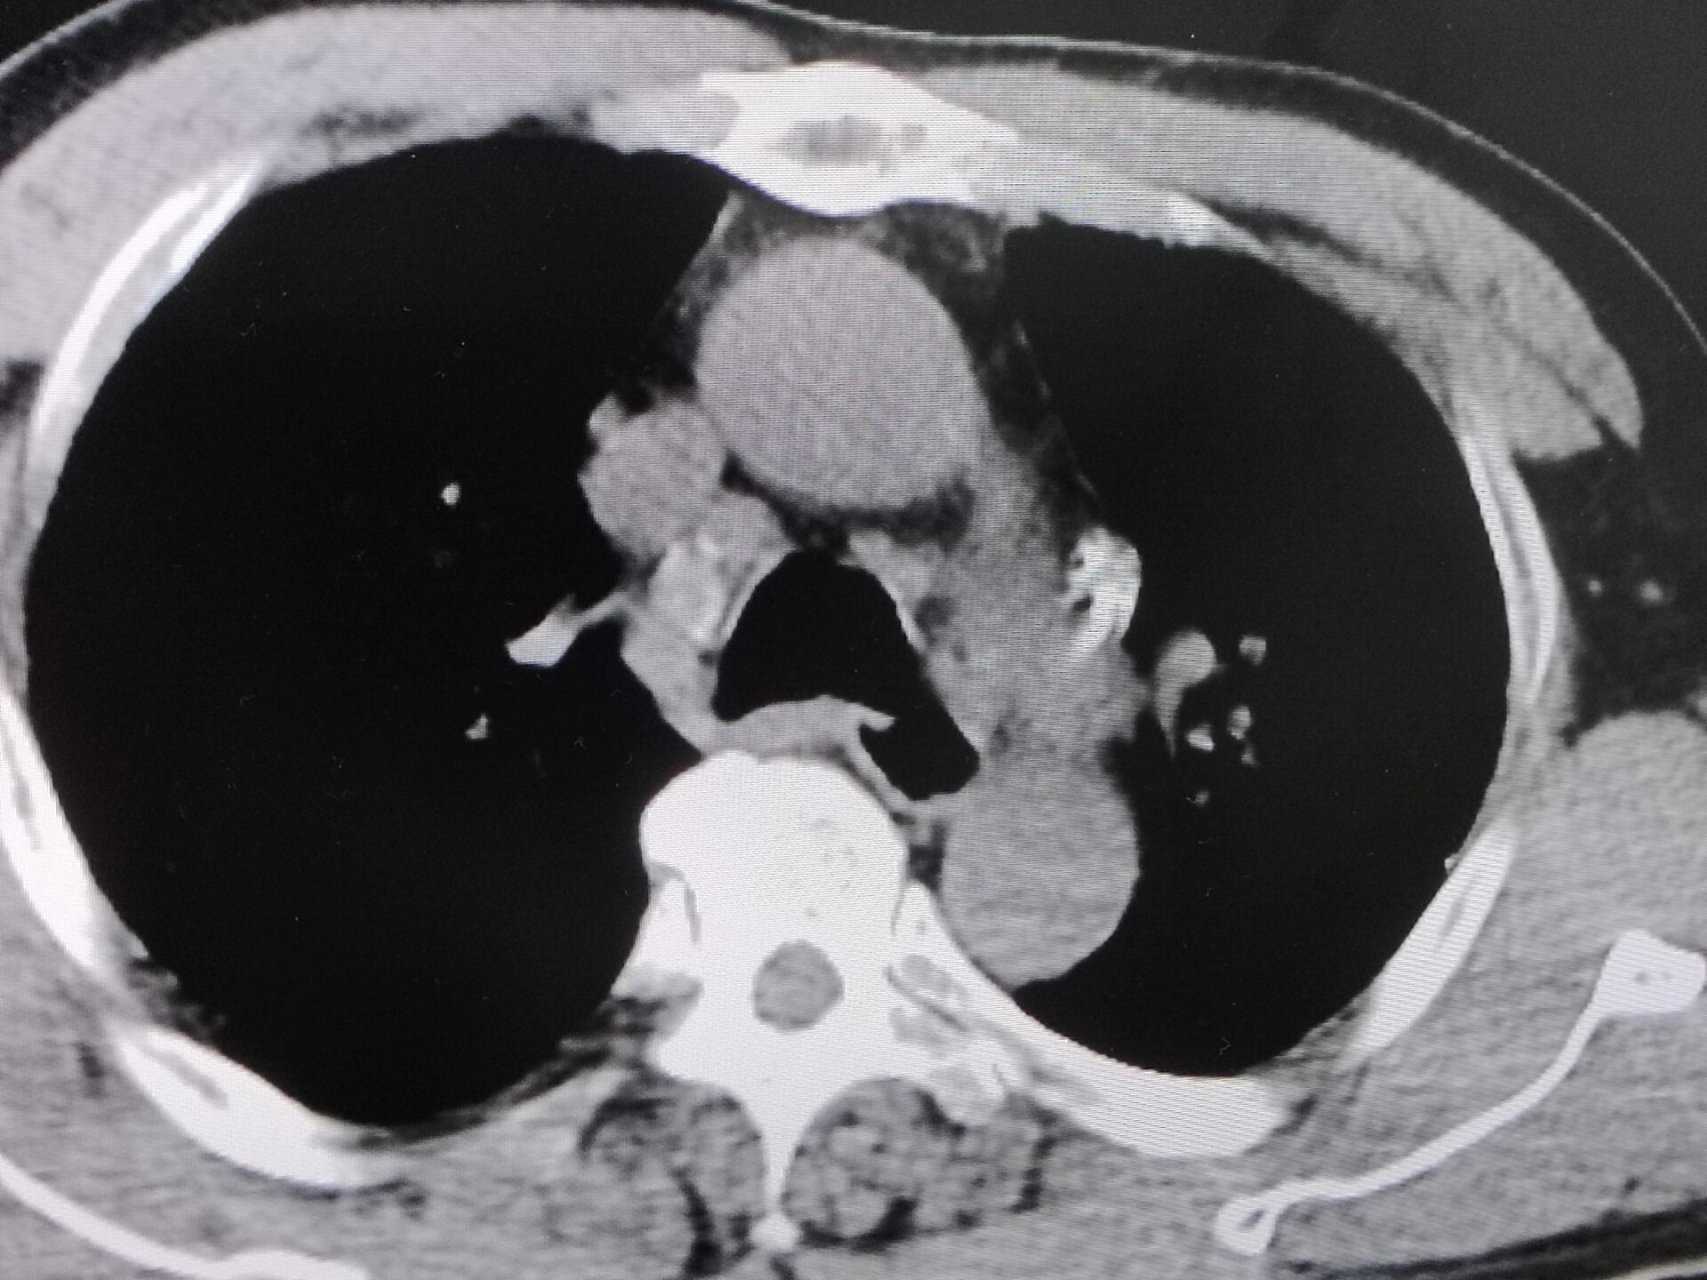

矽肺ct表现 两肺见弥漫多发粟粒结节影,可以看到两肺门,纵隔淋巴结轻